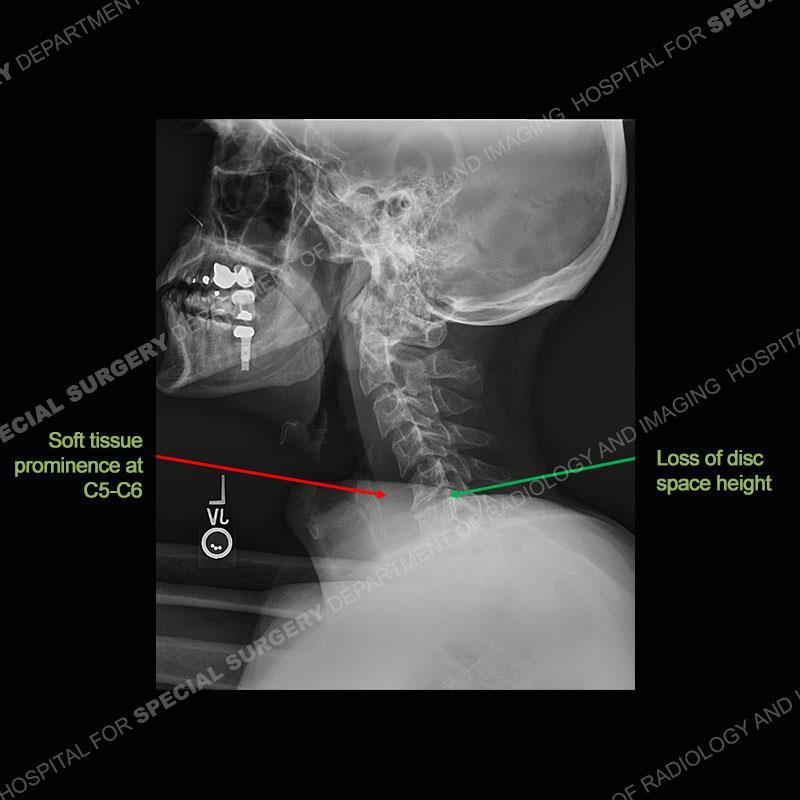

The radiographs demonstrate a prevertebral soft tissue fullness centered at C5-C6 that persists even on extension. There is a slight loss of disc height at C5-C6. The CT more readily shows the prevertebral soft tissue swelling at C5C6 where there is a punctate focus of gas. On the MRI, there is a marked amount of edema and a heterogeneous collection in the prevertebral soft tissue at C5-C6. Edema is present of the C5 and C6 vertebral bodies with a loss of the normal architecture about the disc space. A heterogeneous epidural collection has formed that causes compression of the spinal cord asymmetric to the left side and also precipitates severe left sided neural foraminal stenosis.